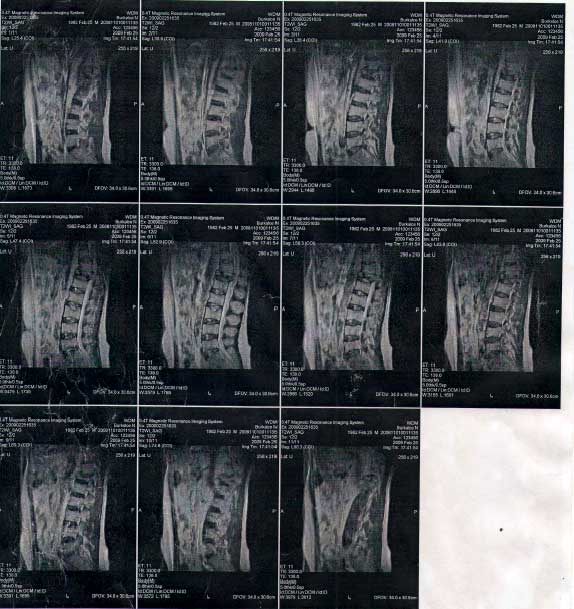

Заключение МРТ: 1 стр. 2 стр. 3 стр. 4 стр.

В 2010 году у Николая из-за диализа развилась болезнь остеопароз, начали разлагаться кости нижних конечностей и произошел компрессионный перелом позвоночника со смещением, был защемлен нерв. С этого времени он ко всем бедам стал лежачим. Мой муж инвалид 1 группы, пенсия у него небольшая, денег лечение совсем не хватает